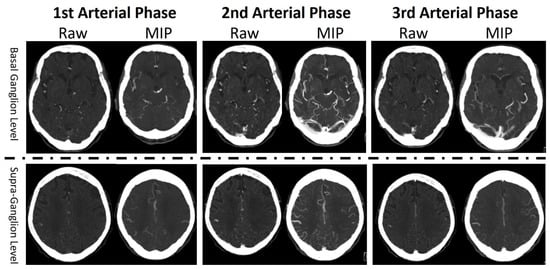

2.2. Imaging Studies

2.3. Data Preprocessing and Normalization